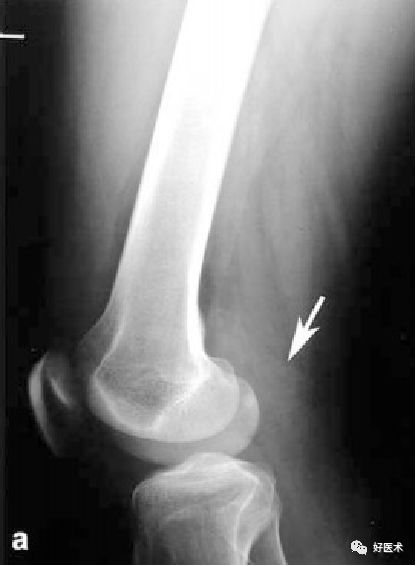

X线

第一期:早期病变,无任何X线表现;

第二期:滑膜炎表现,髌上囊肿胀,因关节积液为血性,故密度稍高;接着出现骨腐蚀和囊性变——实际上是结节在骨软骨上的压迹,以发生在髋关节最为多见;

第三期:进展期,滑膜上有多个软组织结节形成,虽未钙化,但含铁血黄素的密度高,在X线片往往可以显示出结节上轮廓,具有诊断价值。